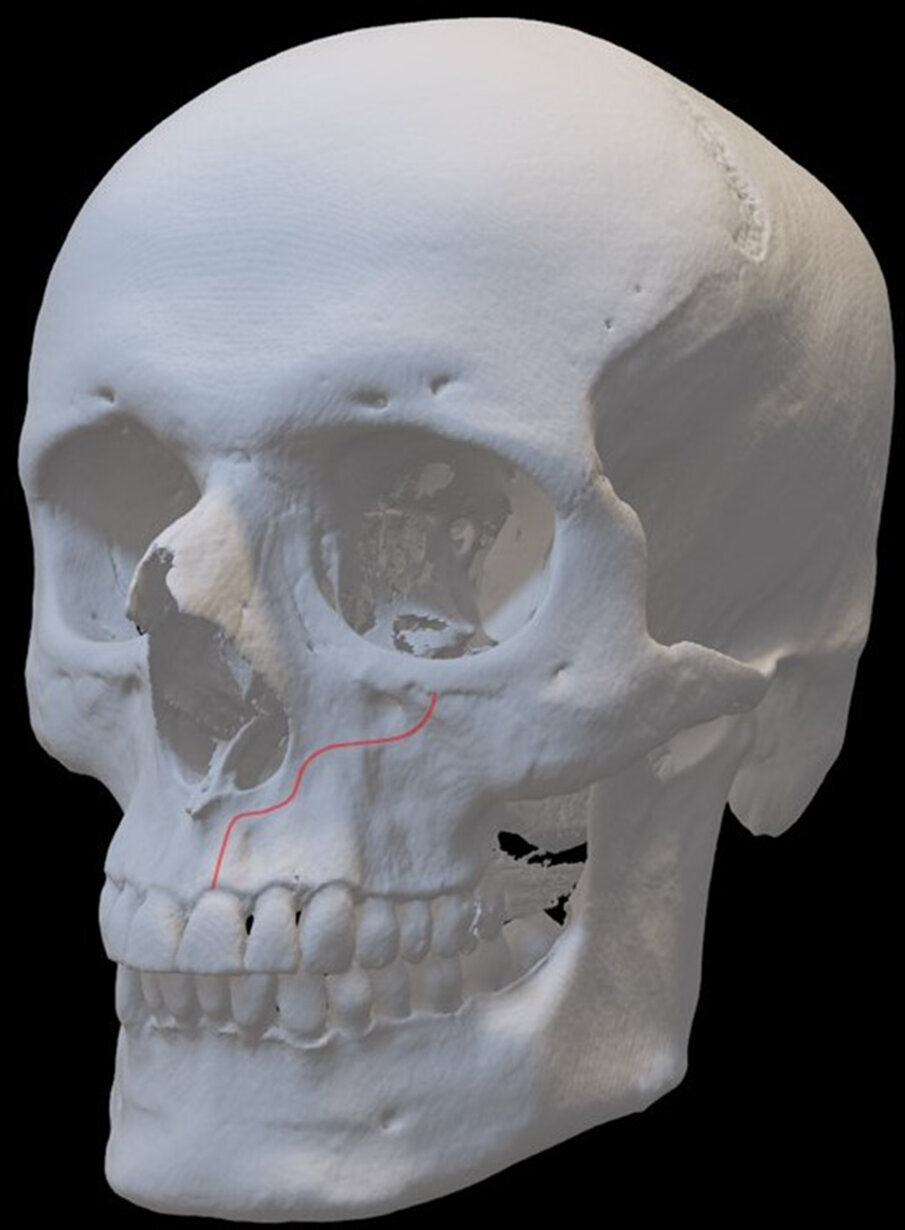

Il nervo infraorbitario, branca del nervo mascellare che è la seconda divisione del trigemino dà la sensibilità alla cute e alle mucose del terzo medio del volto, emergendo dal corrispondente forame si divide in 3 branche alveolari prossimali (i nervi alveolari superiori anteriore, medio e posteriore) e 4 branche distali (palpebrale inferiore, nasale esterno, nasale interno e labiale superiore). Il CS è un tortuoso canale infraosseo (Figg. 1, 2), origina dal nervo infraorbitario, posteriormente al forame di quest’ultimo e decorre in direzione antero-laterale sino alla parete anteriore della fossa nasale al di sotto del margine orbitario, a questo punto vira bruscamente verso il basso lungo l’apertura piriforme descrivendo un andamento ad S per poi dirigersi verso il basso ed emergere nella mucosa palatina attraverso un forame accessorio.

Il termine Canalis Sinuosus (CS) descrive l’andamento a doppia curvatura di quest’ultimo che scorre per circa 55 mm attraverso il mascellare ed è caratterizzato da un sottile osso sovrastante che lo rende più suscettibile a lesioni in caso di trauma. Per questo motivo è considerato un ramo importante del nervo infraorbitario (ION), al suo interno decorrono il nervo alveolare superiore anteriore (ASAN) e vene ed arterie corrispondenti. Infatti, il nervo alveolare antero-superiore (ASAN) è una divisione del ramo mascellare del nervo trigemino che segue un decorso intraosseo nel CS attraverso il mascellare anteriore per innervare gli incisivi ed i canini (Fig. 3). Nel suo terzo finale il nervo alveolare antero-superiore è caratterizzato dalla presenza di molteplici connessioni nervose che possono garantire, in caso di danno, la percezione della sensibilità della zona innervata. La presenza di un CS e di forami accessori (Fig. 4) è spesso ignorata nella pratica chirurgica poiché queste varianti anatomiche possono solo essere rilevate da un attento esame delle immagini radiologiche pre-operatorie, inoltre la loro presenza potrebbe influire direttamente sul successo terapeutico1-5.

Fig. 1 - Decorso del CS simulato in un volume (rendering).